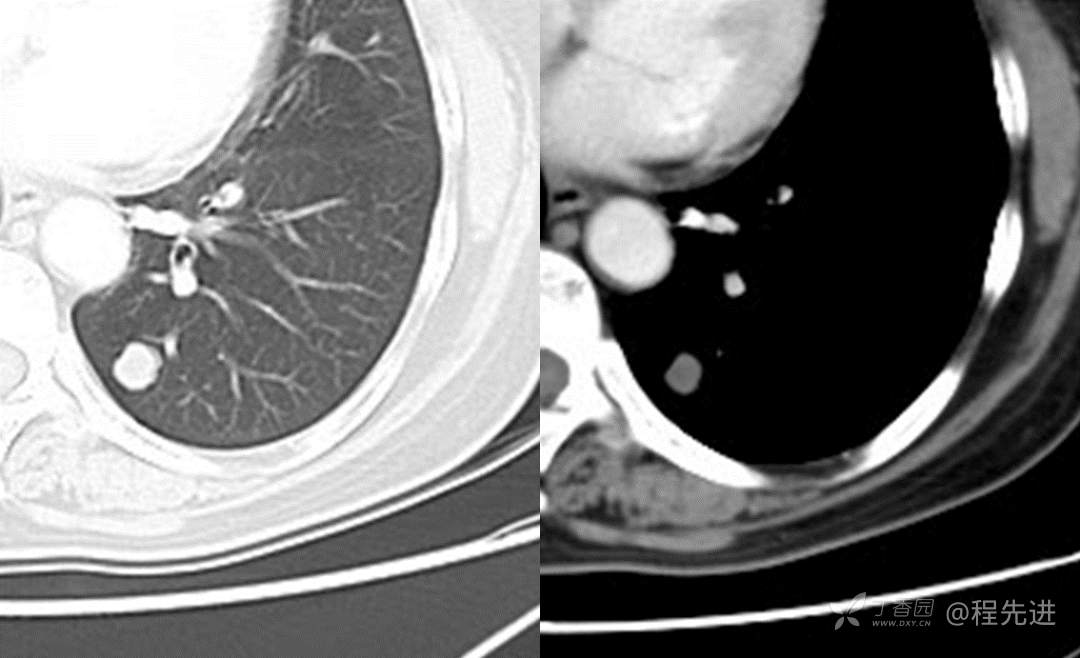

另见:左肺下叶实性结节